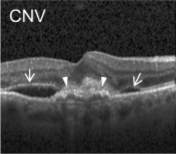

Eye diseases or ocular dysfunctions are fairly frequent in the general population, particularly among the elderly. The most significant anomalies in the eyes are choroidal neovascularization (CNV), diabetic macular edema (DME), and drusen accumulation in the macular region. In the recent decade, optical coherence tomography (OCT) has become one of the most rapidly evolving medical imaging technologies which can capture blood flow, polarization state, structural data, elastic properties, and molecular content, among other things, in biological tissues [1]. Optical diffraction and absorbance of biological tissues can be accurately measured with OCT and thus some diagnostic measures benefit from it.

Figure 1: Representative Optical Coherence Tomography (OCT) Images (a) CNV (b) DME (c) DRUSEN (d) NORMAL

Optical coherence tomography (OCT) images were selected from retrospective cohorts of adult patients from different hospitals around the world. OCT Images are labeled as (disease)-(randomized patient ID)-(image number by this patient) [11] and Fig 1 shows some examples of OCT images. Image properties are presented in Table II and the distribution of image quantity is presented in Table III. Custom image generators resize images to 224x224x3 and normalize them